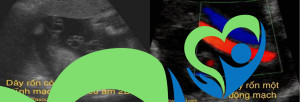

HIỂU VỀ TÁC DỤNG CỦA SIÊU ÂM TRONG QUÁ TRÌNH CHUYỂN DẠ

Chuyển dạ là thời điểm rất được quan tâm, bên cạnh khám bằng tay thì siêu âm để đánh giá cũng đóng vai trò quan trọng. Trong những trường hợp như ngôi thai bất thường, thai chậm phát triển, quá trình chuyển dạ chậm hay ngừng tiến triển thì siêu...